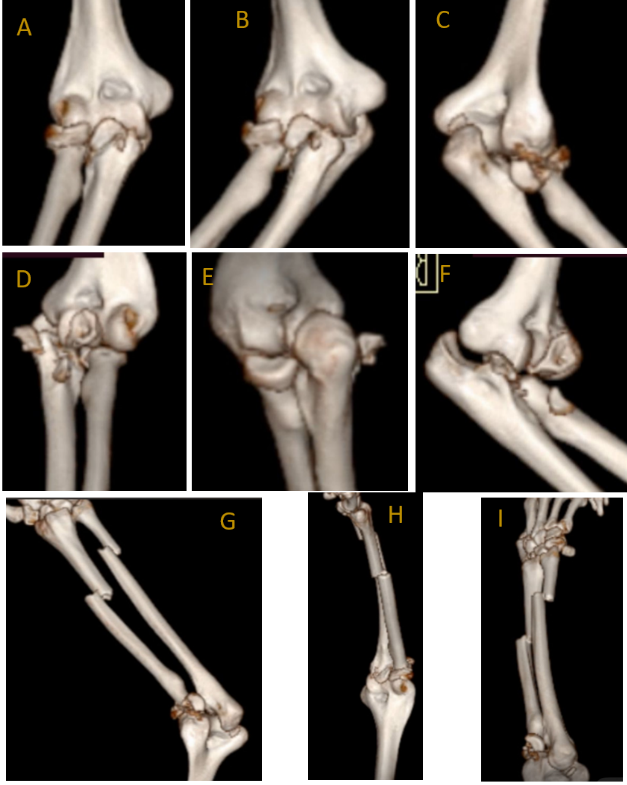

A right-hand dominant male in his late 20s, with a known history of schizophrenia on regular medication, presented to the emergency department of a tertiary care center after sustaining a fall from a height of 18 feet. On arrival, he was managed according to advanced trauma life support protocols. The primary survey was conducted immediately, confirming a patent airway with cervical spine protection, spontaneous breathing with symmetrical chest movement, and hemodynamic stability (C-spine cleared clinically and later radiologically). Circulation was assessed with bilateral feeble lower limb pulses, and intravenous access was established. There were no signs of active bleeding or tension pneumothorax. A focused neurological examination revealed that the patient was conscious and oriented, with no evidence of head injury or spinal cord involvement. Secondary survey revealed multiple orthopedic injuries and soft-tissue wounds over bilateral limbs, resulting in swelling and restricted ROM in both elbows, left knee, and both ankles, along with pain and tenderness over the lower back. Initial radiographic (Fig. 1) and clinical assessments revealed closed terrible triad injury of the right elbow and an open grade 1 terrible triad injury on the left elbow, i.e., bilateral dislocation of elbows, with radial head (right- Mason type III, left- Mason type IV) and coronoid process-associated fractures (Regan–Morrey type III- right, type II- left). Additional injuries included a right-side forearm fracture, comminuted open grade 2 distal femur and patella fracture on the left side, undisplaced fractures of the scaphoid, lunate, triquetrum, and distal radius on the left, open calcaneal and talar fractures on the right, closed pilon fracture, L1 vertebral body fracture (AO Type C), and multiple metatarsal and cuneiform fractures of the left foot. Three-dimensional (3D) computed tomography reconstruction of the elbows showed coronoid process fracture and comminuted radial head fracture on both sides (Fig. 2).

Figure 2: Pre-operative computed tomography scan 3D reconstruction of right elbow (a, b, c) and left elbow (d, e, f), right elbow with forearm (g, h, i).